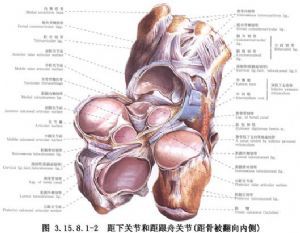

距下(距跟)、距舟、跟骰关节融合称三关节融合。虽是最早设计的方法,但目前这种方法仍然是最常使用的手术。手术原则旨在楔形切除距下关节纠正内翻,切除跟骰、距舟关节,纠正前足内收和内翻,楔形切除的底边方向相反,也可纠正足外展和外翻畸形。手术相关解剖见下图(图3.15.8.1-1,3.15.8.1-2)。

局部解剖示意图见12.27.1.6-1。